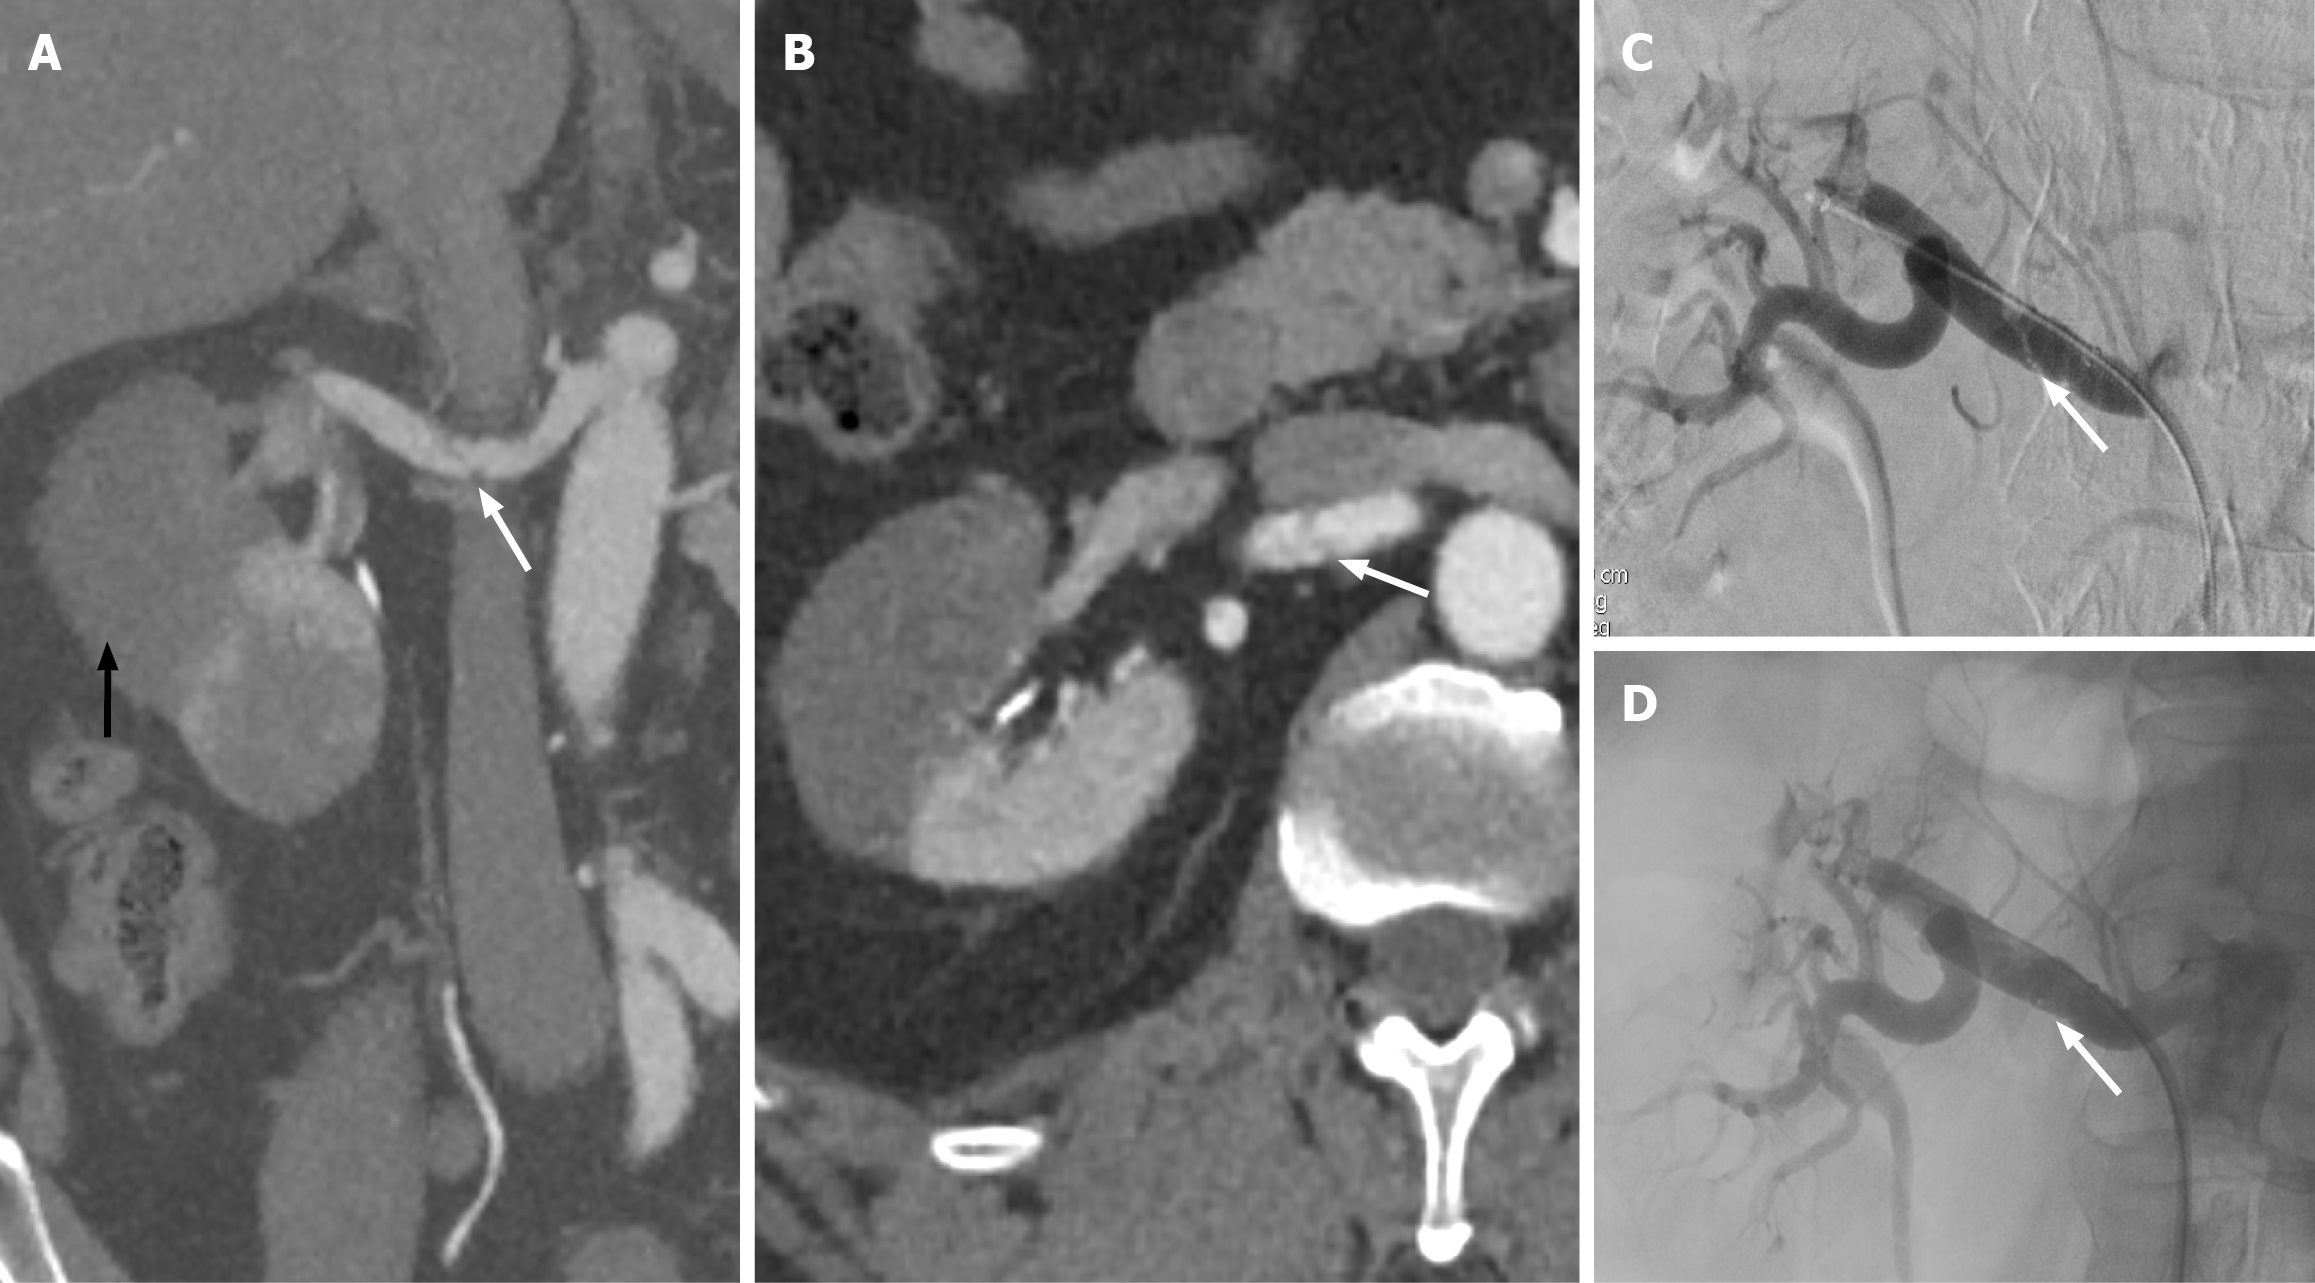

Figure 7 Renal artery dissection.

A: Coronal view computed tomography of the abdomen in arterial phase demonstrates linear hypoattenuation within the right mid renal artery, suggesting dissection (white arrow). Note the infarcted kidney (black arrow); B: Axial view confirming the dissection flap within the right renal artery (white arrow); C: Right renal angiogram demonstrating the dissection flap within the right renal artery (white arrow); D: Successful stenting of the right renal artery (white arrow).